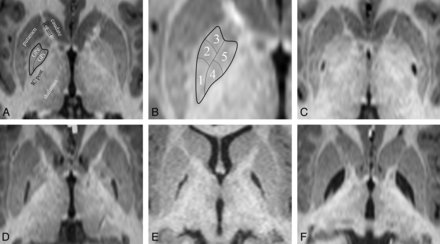

On review of the GP infarcts as a group, it became apparent that the infarct pattern was not random and that some segments of the GP infarcted more often than others. The 5 infarct-delineated segments are shown in Fig 4. There appear to be 3 distinct segments in the globus pallidus externa (GPe) and 2 distinct segments in the globus pallidus interna (GPi). When the affected segments were all displayed as a group (Fig 5), it appeared that the segments were affected sequentially, with a few exceptions (5 of 38 infarcts in 3 of 19 patients). This observation suggested a staging system, in which the infarct stage is determined by counting the number of affected segments. According to this staging system, we observed 10 stage 1 infarcts, 7 stage 2 infarcts, 7 stage 3 infarcts, 3 stage 4 infarcts, and 11 stage 5 infarcts. In 3 patients, the right and left stages were discordant.

GP infarct segments. A, Normal anatomy of the dorsal pallidum, also known as the globus pallidus. The thin line indicates the medial medullary lamina; the thick line, the boundary of the globus pallidus. Surrounding structures include the anterior limb of the internal capsule (IC ant) and the posterior limb of the internal capsule (IC post). The putamen, thalamus, and head of the caudate nucleus are also labeled. The external medullary lamina separates the putamen from the GPe. B, Infarct segments 1–5. Segment 1 seems to be the most sensitive to metabolic infarct in MMA, followed by segment 2, then segment 3; segments 4 and 5 are the least sensitive and usually infarct together. C, An example of a segment 1 infarct (posterior GPe). D, An example of an infarct of segments 1 + 2 (posterior and middle GPe). E, An example of an infarct of segments 1 + 2 + 3 (whole GPe). F, An example of an infarct of segments 1 + 2 +3 + 4 + 5 (complete GP, both externa and interna). Note that the medial medullary lamina (a white matter tract) remains intact and can be seen separating the GPe and GPi.

Graphic depiction of all 38 GP infarcts. Infarcted segments are shown in black (follows the rule) or gray (exception to the rule). The segments appear to follow a rule in which the likelihood of infarct is 1 > 2 > 3 > 4 = 5. Five infarcts (in 3 different patients) do not follow the segment-ordering rule. Infarcts can be staged by counting the number of infarcted segments, regardless of the order. In 16 of 19 patients, right and left infarcts are of the same stage, even if the volumes differ (as described in Fig 2). The location of the segments is shown in Fig 4.

The GPe appeared to be more vulnerable to metabolic infarct than the GPi. In fact, only 1 infarct had any part of the GPi involved without involving the entire GPe. Within the GPe, vulnerability appeared highest in the most posterior segment and lowest in the most anterior segment, though there were 4 exceptions to that pattern. GPi vulnerability would seem to be fairly homogeneous, though there were 2 exceptions in which only half of the GPi was infarcted; in one case, only the posterior half was involved, and in the other case, only the anterior half was involved.